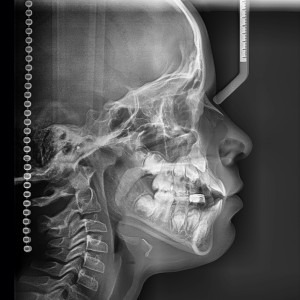

SERVICIOS 2D

SIALOGRAFIA